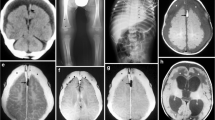

SDH is well demonstrated on screening CT, but detection and characterization both benefit from the improved spatial and contrast resolution of MR [19, 20, 58]. Associated bridging vein thrombosis may be evident as hyperdensity on CT or hypointensity on susceptibility-sensitive MR sequences (T2* or SWI), with linear intravascular thrombus extending into more globular extravascular clot at the site of vessel rupture near the vertex. This appearance has been termed the “tadpole” [55••] or “lollipop” [56•] sign (Fig. 1).

3-month-old male presented with seizures, bruising, subconjunctival hemorrhages, and multilayered RH. a Axial T2-weighted image shows focal enlargement of a parasagittal bridging vein near the vertex (white arrows), suggesting vein rupture. b Axial SWI image demonstrates marked hypointensity and blooming within the distal vein and at site of venous rupture (white arrows), confirming thrombosis. This appearance has been termed the “tadpole” or “lollipop” sign. Thin left SDH is evident as crescentic blooming artifact on the SWI image

The parenchymal injury associated with AHT may be occult on early screening CT, or may be seen as diffuse or hemispheric hypodensity with evidence of mass effect. Thin SDH associated with disproportionate ipsilateral hemispheric mass effect on screening CT should raise the possibility of early unilateral HII and prompt consideration of AHT and further evaluation with MRI (Fig. 5).

Two and half-year-old male presented with seizure and decreased level of consciousness following unwitnessed fall down 2 stairs. Initially misdiagnosed as stroke at OSH and transferred to tertiary care hospital for rehabilitation, patient was noted to have multiple healing fractures and diffuse multilayered RH on further evaluation. a Initial CT from OSH demonstrated thin right SDH with disproportionate mass effect resulting in right to left midline shift. b Axial FLAIR image from subsequent MR demonstrates diffuse unilateral cortical hyperintensity on the right. c Axial ADC map demonstrates a predominately subcortical pattern of diffusion restriction

Early injury is better demonstrated on MRI. T2 hyperintensity reflecting tissue edema may be subtle in the unmyelinated brain, and DWI will dramatically increase conspicuity of cytotoxic injury [100]. Studies examining the patterns of diffusion restriction in AHT have suggested a watershed pattern of HII in a majority of cases [93, 100, 101]. However, multiple patterns of parenchymal injury are potentially consistent with AHT (Fig. 6).

Parenchymal lacerations or contusional clefts appear as linear tears in the brain parenchyma, predominately within the cortex or at the gray-white junction of the gyral crests. They predominate in the frontal and temporal lobes. They frequently demonstrate layering sedimentation levels on both CT and MR (Fig. 7). When superficial, they can be associated with overlying subpial hemorrhage.

6-week-old female presented with vomiting, seizures, abnormal breathing, abdominal bruising, and facial abrasions. a Axial-unenhanced head CT image shows hyperdense (acute) right frontal subdural hemorrhage (black arrows) and a hypodense left frontal cleft containing dependent hyperdense blood (white arrows). b, c Axial T2-weighted and SWI images show the acute blood products as T2 hypointense material in the subdural space (black arrows) and layering within the contusional tear (white arrows)

RH has not traditionally been considered an imaging diagnosis, although it has occasionally been reported [114]. It presents as high-attenuation foci at the posterior globes on CT, and low-signal foci on MR sequences (Fig. 8).

4-month-old male presented with seizures and decreased level of consciousness. Dilated fundoscopic examination demonstrated multilayered retinal hemorrhage with a macular schisis cavities in the bilateral eyes. a Axial T2-weighted image demonstrates retinoschisis of the posterior globes bilaterally (white arrows). b Axial SWI images demonstrate increased conspicuity due to blooming artifact (white arrows), confirming RH

Skull Fractures

Skull fractures are not specific for AHT. Non-displaced linear skull fractures and associated small volume subperiosteal hemorrhage are common findings in low-impact nAHT, such as with short-distance falls [42••]. Contradictory data exist regarding which features, if any, may increase the specificity of skull fractures for AHT [117–119]. Fractures which are multiple, complex, diastatic, or growing suggest a high-energy mechanism and are concerning in the absence of appropriate history (Fig. 9).

1-year-old male presented with head injury after mother’s boyfriend “fell on him” while removing him from his car seat. a Axial-unenhanced CT image shows impact injury pattern with scalp swelling and cephalohematoma (white arrows), diastatic right occipital fracture, and hemorrhagic contusion (black arrows). b Volume-rendered CT image demonstrates complex occipitoparietal fractures crossing sutures (white arrows), with fracture diastasis (black arrows). c Volume-rendered CT image at 2-month follow-up redemonstrates complex fractures (black arrows), with increasing diastasis of the displaced fracture suggesting a “growing fracture.” d Volume-rendered T2-weighted MR image after skull stripping demonstrates a large posterior pseudomeningocele or “leptomeningeal cyst” as the cause of the growing fracture

Dating of skull fractures on CT can be difficult, as expected imaging findings associated with healing long bone fractures are not typical. In our experience, blurring of the fracture margins and new bone formation by the intact periosteal layer of dura are features of subacute healing fractures and are inconsistent with recent trauma (Fig. 10). Absence of these features cannot reliably be used to conclude acuity, however. Soft tissue swelling and subgaleal hemorrhage are suggestive of more recent injury but are not universally present in acute injury.

6-month-old male presented with head injury after being stuck with a hammer. a Axial-unenhanced CT image shows an acute diastatic right parietal fracture (black arrows) with associated scalp swelling (white arrows). b Axial-unenhanced CT image performed after 4 weeks shows linear periosteal reaction consistent with healing (black arrows), as well as decreased scalp swelling (white arrows)

MR imaging of the cervical spine is recommended routinely along with MR brain imaging in all cases of suspected AHT. Although an early report demonstrated low sensitivity for detection of CCJ injury with MR in cases of severe AHT [126], this study predated the widespread clinical availability of STIR and other fat saturation techniques that increase the conspicuity of soft tissue and subtle bony injury. Recent studies have demonstrated improved rates of detection of abnormalities at the CCJ with MR [27••, 29•, 120], with ligamentous injury the most commonly reported finding (Fig. 11). Routine utilization of fat-saturated fluid-sensitive sequences is therefore recommended.

6-week-old male found down at home. MR of the brain revealed diffuse HII, bilateral SDH, and bridging vein thrombosis. Left intraretinal RH on dilated fundoscopy. a Sagittal STIR image shows hyperintense signal in the nuchal ligament and underlying posterior cervical fat (white arrows), consistent with ligamentous injury. b Sagittal T1-weighted image shows mildly hyperintense retroclival and thoracolumbar extra-axial collections (white arrows), consistent with subdural hemorrhage